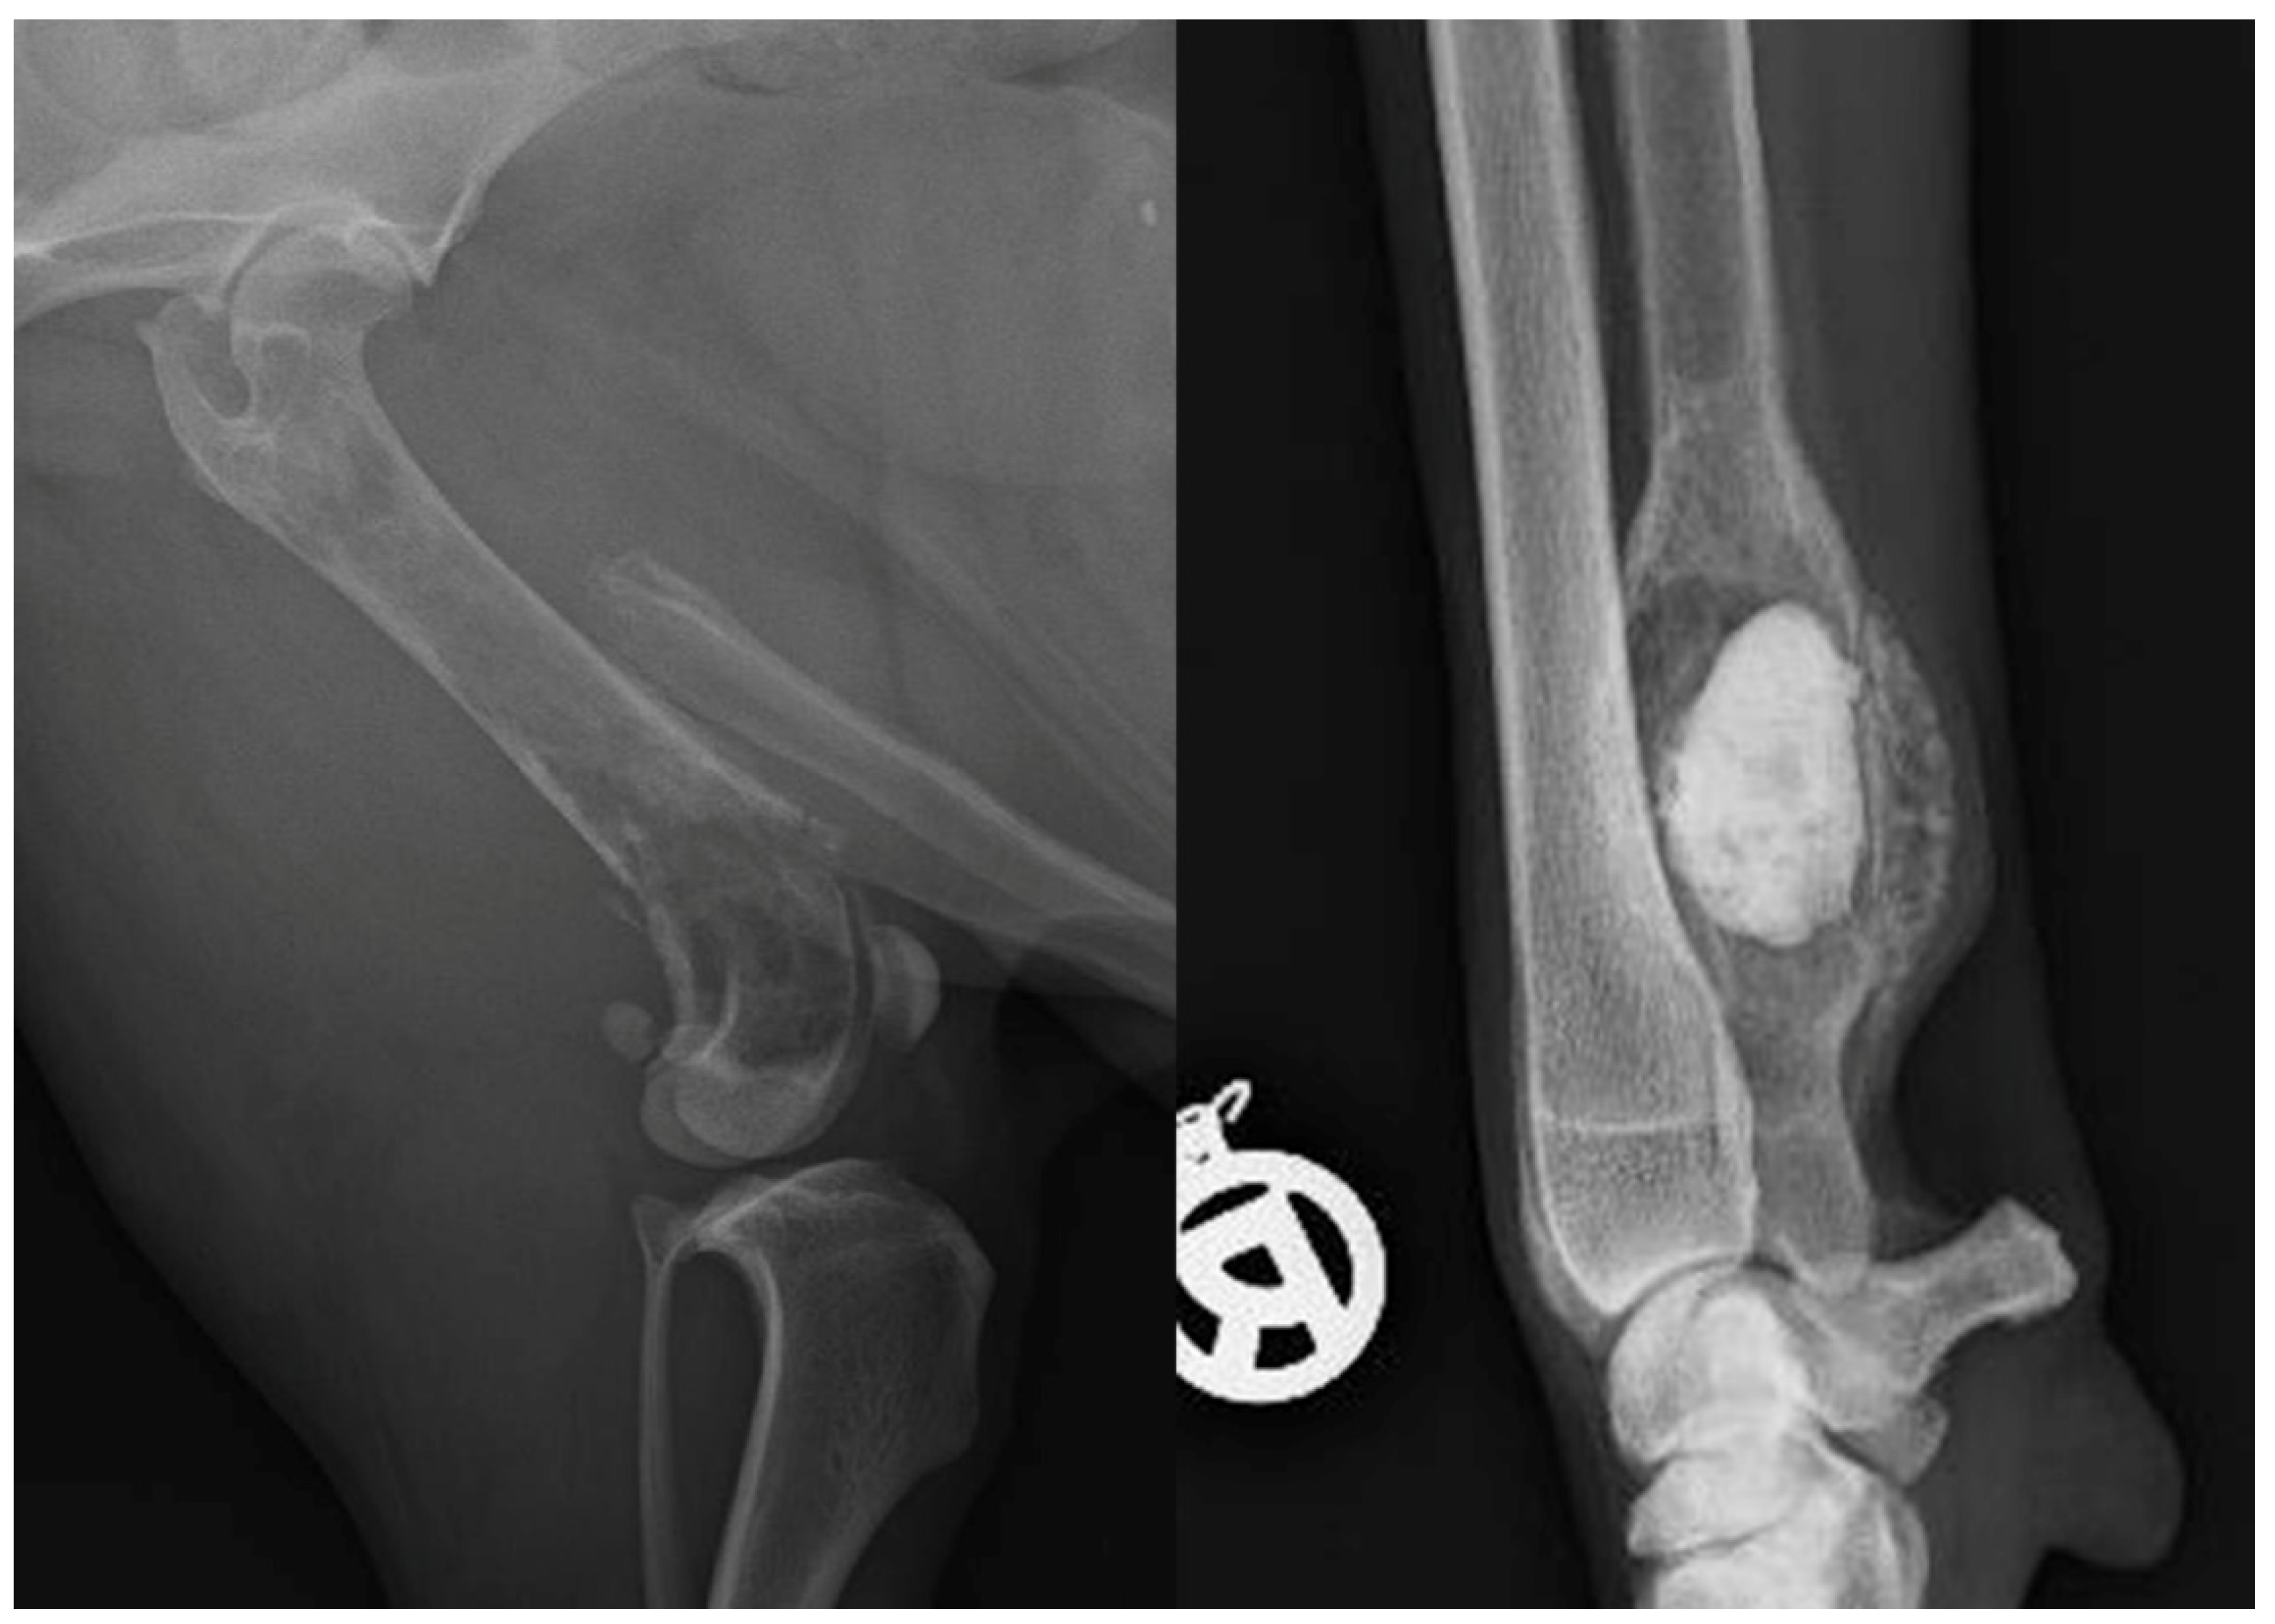

Appendix E. Activity Classifying Singular Bone Lesions

| Criterion | Aggressive Bone Lesion | Non-Aggressive Bone Lesion |

|---|---|---|

| Example | Osteomyelitis, Osteosarcoma | Bone cyst, Osteoma |

| Osteolysis type | Moth-eaten or permeative | geographic |

| Transition zone | Long and poorly demarcated | Well demarcated, eventually showing a sclerotic rim |

| Compact bone | Interrupted | Preserved |

| Periosteal reaction | Interrupted, irregular | Solid, smooth |